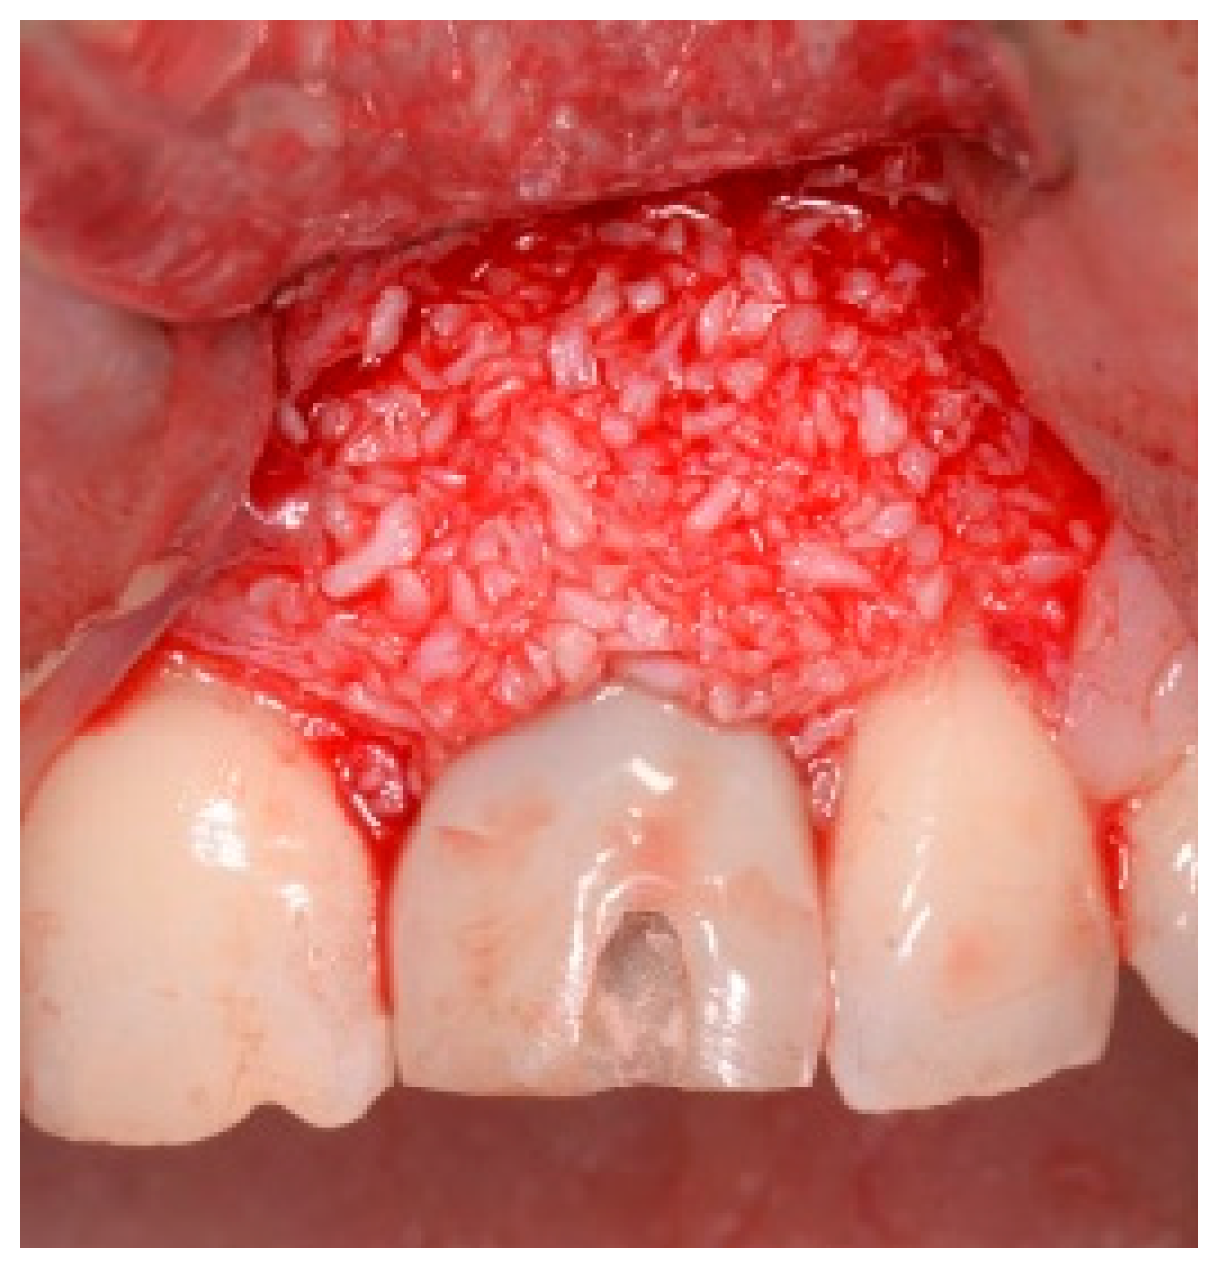

Before the graft and membrane is placed over the defect, a periosteal dissection must be performed to release flap tension to facilitate its coronal advancement and closure. The horizontal incision is made 1 mm deep into the periosteum, apical to the mucogingival junction, in a single plane along the length of the flap, connecting the two vertical releasing incisions. After the placement of this shallow incision, a micro-elevator is used to stretch within the incision line. This stretching not only releases the tension within the flap but also allows a more coronal advancement of the flap margin for eventual primary closure, minimizing postoperative incision line opening. This important step in flap management is performed before the placement of the graft material because the periosteal-releasing incision is associated with increased bleeding, which will complicate the graft, the membrane placement, and stabilization. A composite graft material consisting of allograft and xenograft in a 50/50 mix was placed in the gap between the implant and the socket wall over-contouring the facial wall defect (Figure 4). Two healing abutments were placed on the implants, followed by a bioabsorbable collagen membrane (Zmatrix, Osteogenics, Lubbock, TX 79424, USA) placed over the surgical area, which was closed with 5.0 polypropylene sutures (Figure 5). An Essex appliance, fabricated inhouse using a standard suck-down process, was inserted postsurgically. The implants were allowed to heal in a non-submerged environment for a period of 6 months.

Figure 4.

Clinical view post graphing.